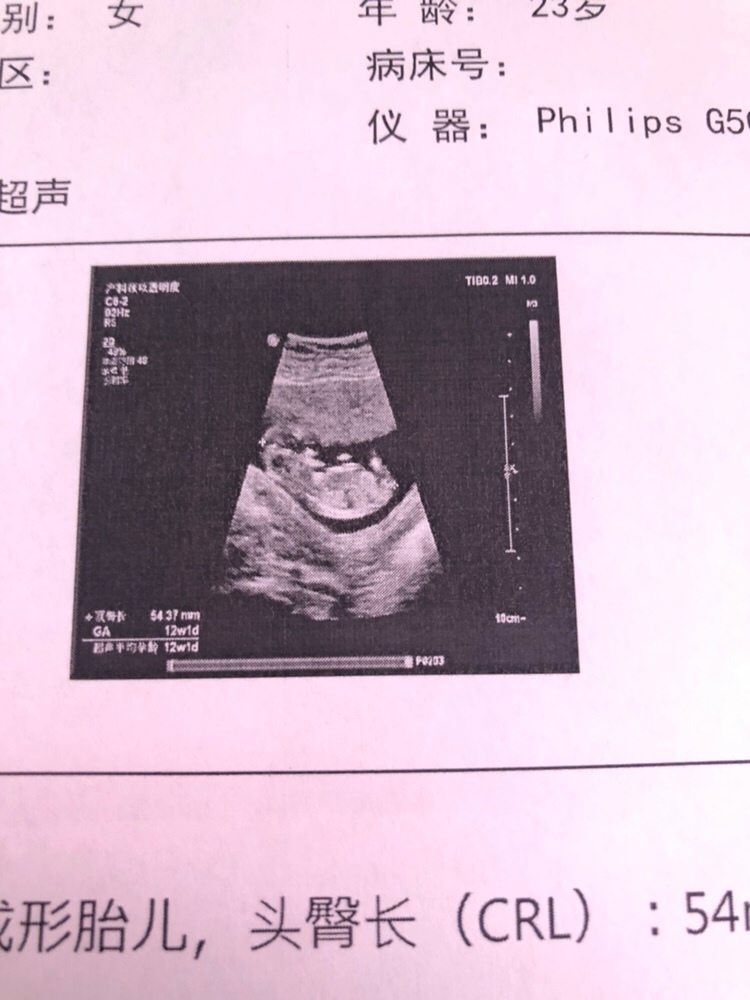

男女都好,哈哈,接Nt顺利通过,有人说胎心160以上是女宝,胎心160以下是男宝,还是生下来靠谱